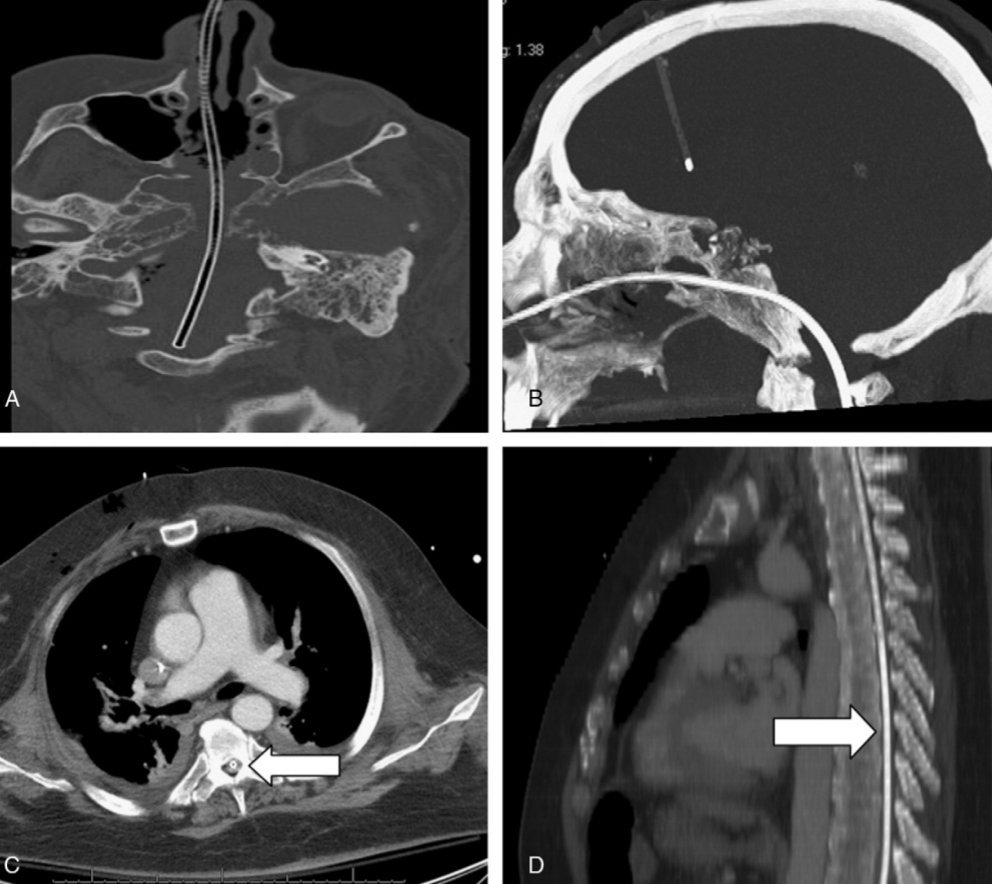

1.

#Cirugía base de cráneo x cordoma del clivus

57a

2. Se le colocó sonda nasogástrica antes.

3. En UTI el paciente se la saco.

4. El #Médico de guardia la recolocó: la sonda atravesó la base del cráneo reparada, el tronco del encéfalo y entró a la médula. 5. Caudraplejia y

pic.twitter.com/oJ97Hrjl7Y